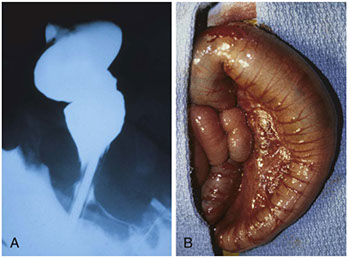

Hirschsprung disease. A) preoperative barium enema showing constricted rectum and dilated sigmoid colon. B) corresponding intraoperative photo showing constricted rectum and dilation of the sigmoid colon